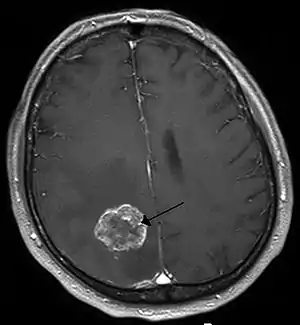

| Brain metastasis in the right cerebral hemisphere from lung cancer, shown on magnetic resonance imaging | |